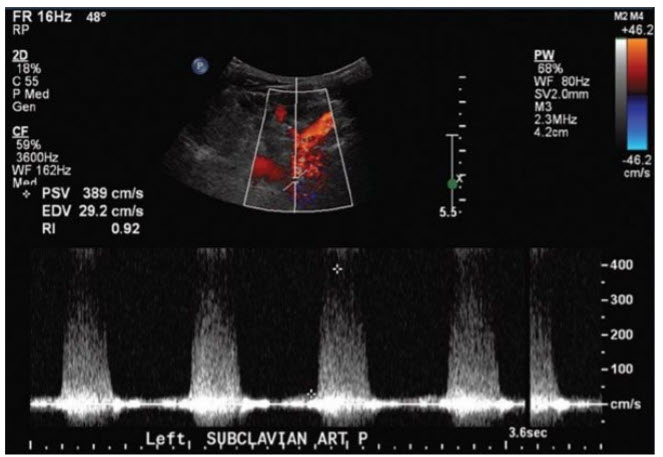

A 64-year-old woman presents to the clinic for evaluation prior to coronary artery bypass surgery. She underwent carotid duplex ultrasound demonstrating normal bilateral internal carotid arteries. Images from her scan are illustrated in Figure below.

What unexpected condition is demonstrated by her ultrasound images?

Subclavian artery stenosis. Color Doppler imaging shows significant color aliasing, spectral broadening, and turbulent high-velocity flow within the subclavian artery. It is important to recognize severe subclavian artery stenosis prior to coronary artery bypass surgery in which the internal mammary artery may be utilized. Severe subclavian artery stenosis can lead to retrograde flow in the internal mammary artery predisposing to early graft failure. In an aneurysm usually the velocities are decreased.